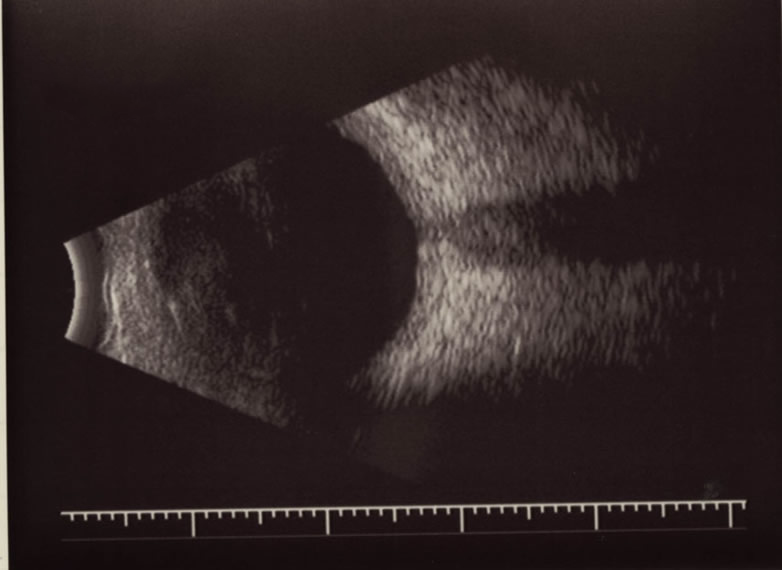

B‐モード

急性期原田病におけるB‐モード所見。著明な脈絡膜浮腫が観察できる。

出典

img

1: 大黒伸行先生ご提供